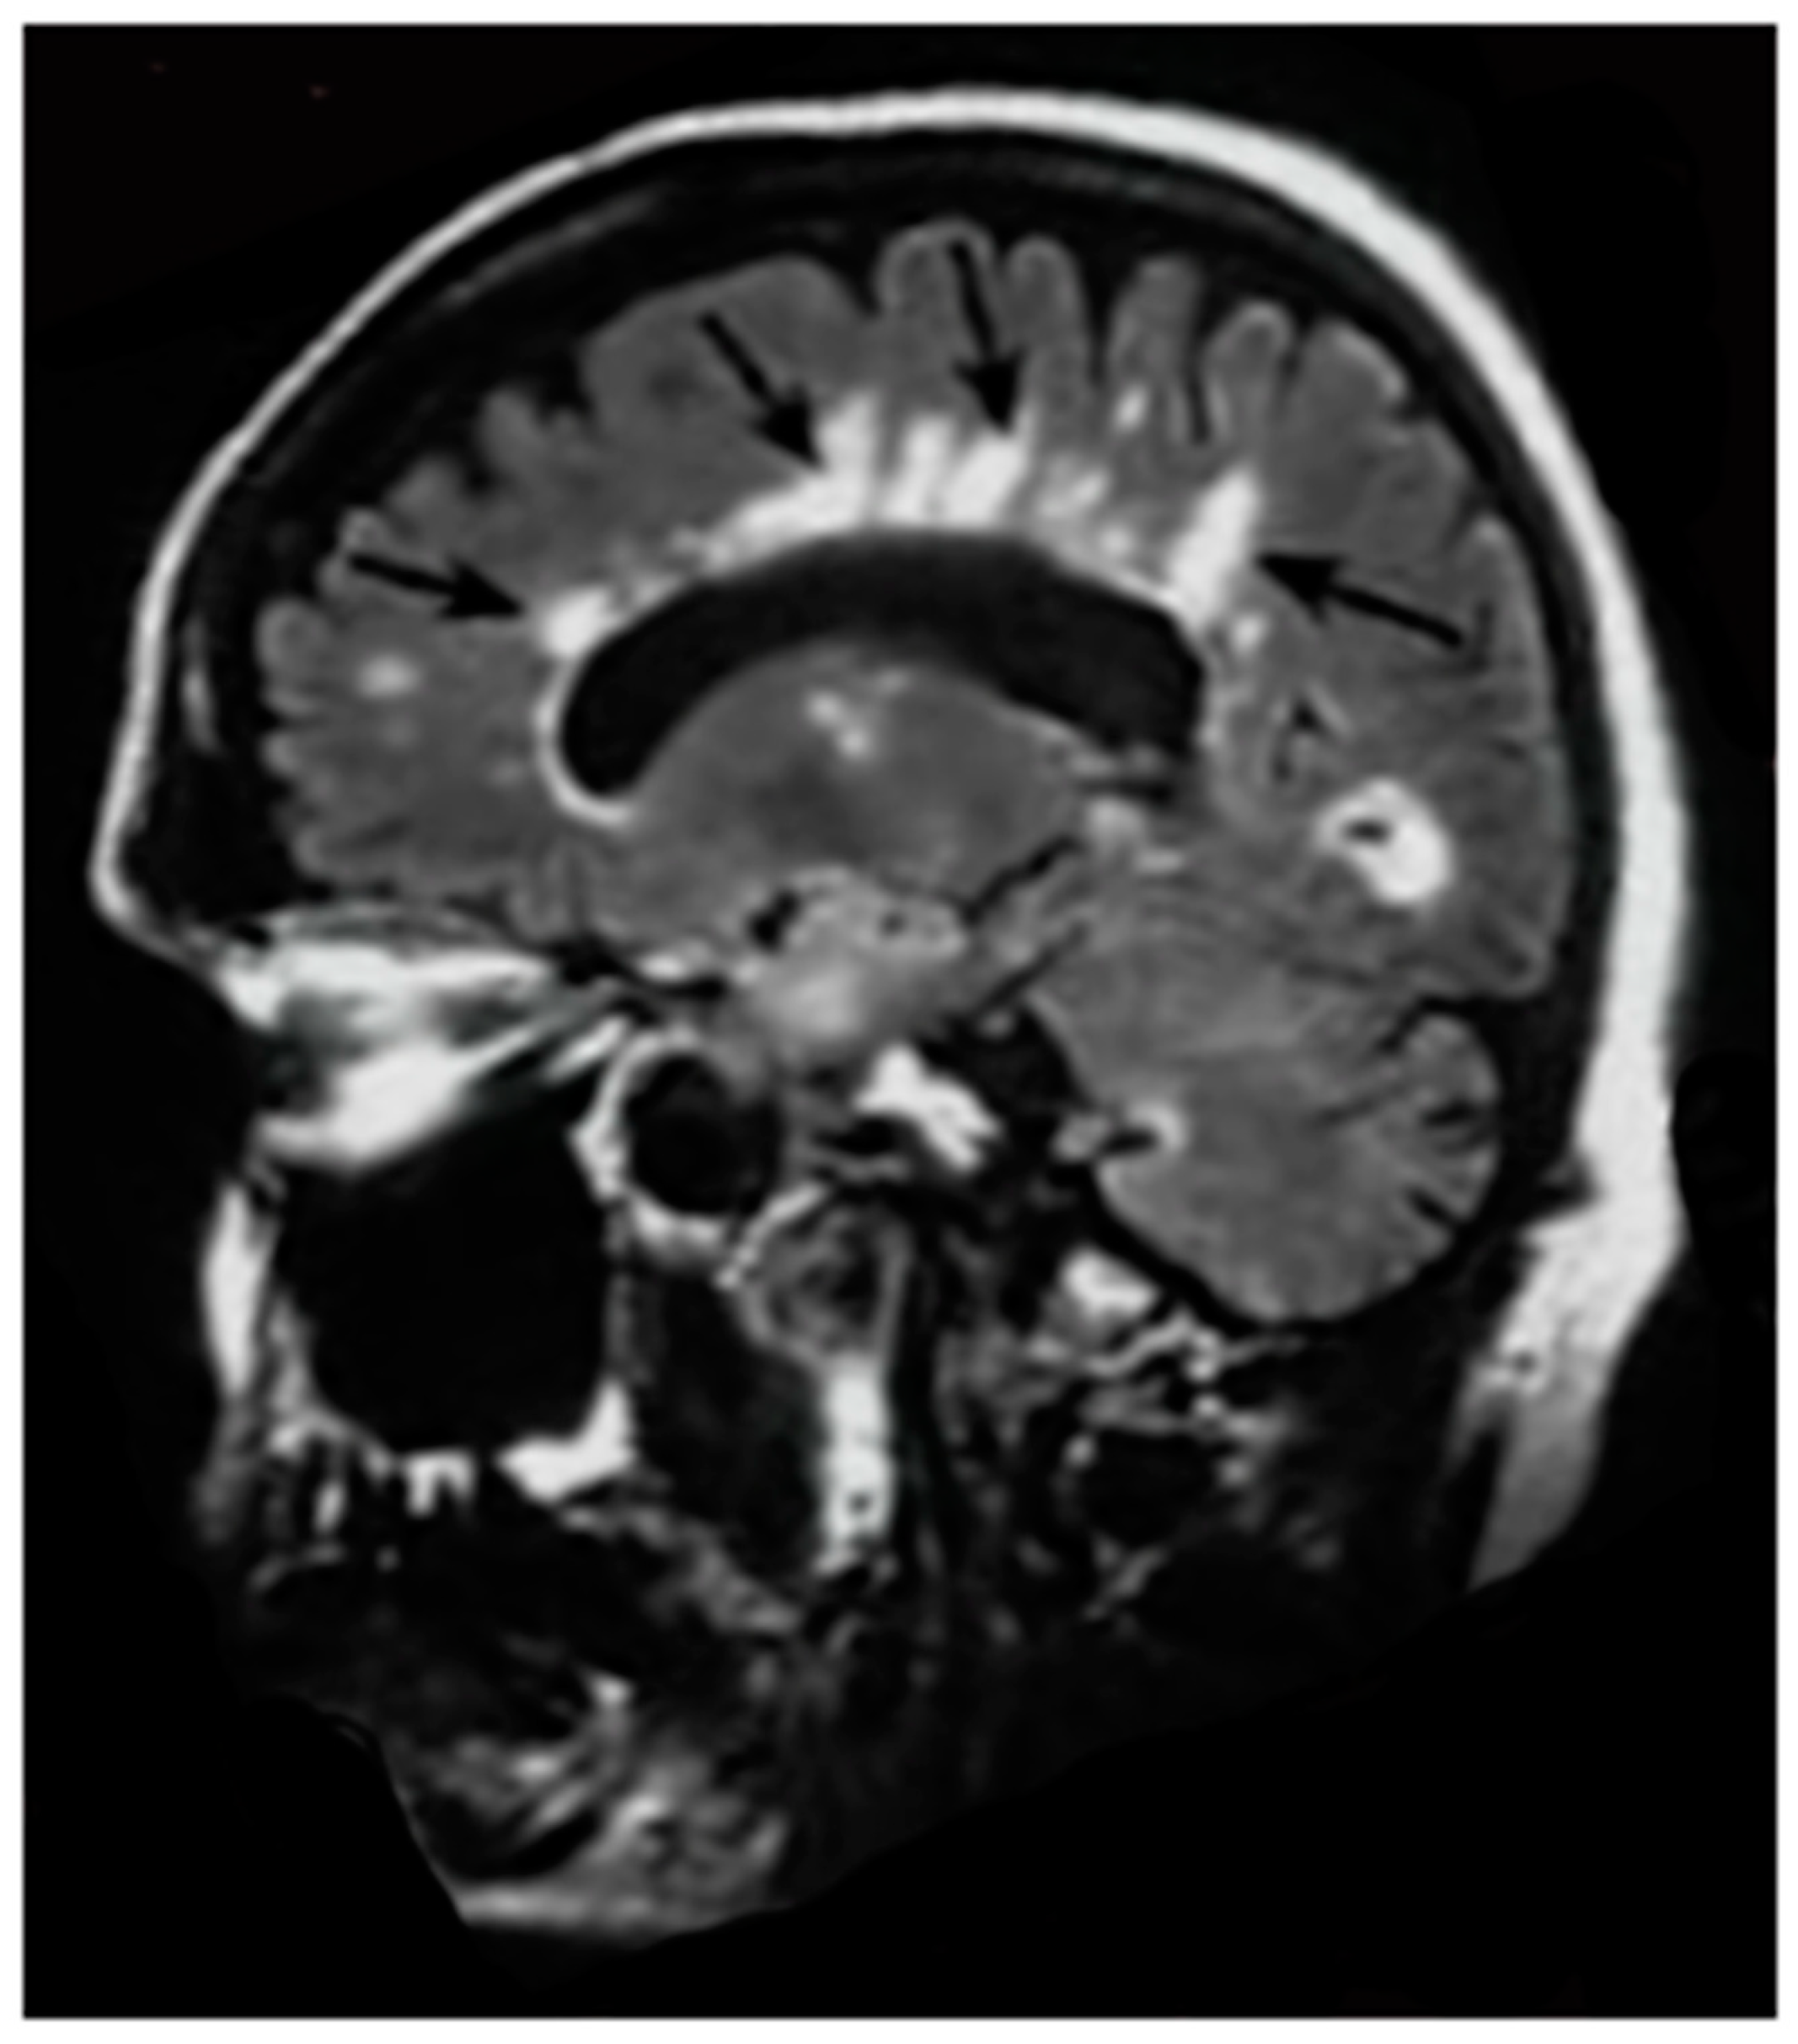

Grinker’s myelinopathy or delayed post-hypoxic leukoencephalopathy may produce extensive white matter changes that are obvious on T2-wFSE and/or T2-FLAIR images. The condition is thought to be rare. The whiteout sign seen in post-hypoxic patients on dSIR images may actually be a less severe form of the changes seen in Grinker’s myelinopathy in which changes are not seen with T2-wFSE and T2-FLAIR images [19]. It is therefore possible that Grinker’s myelinopathy is much more common than usually thought, but is not recognized because the changes in white matter are usually insufficient to produce diagnostic contrast with conventional sequences.